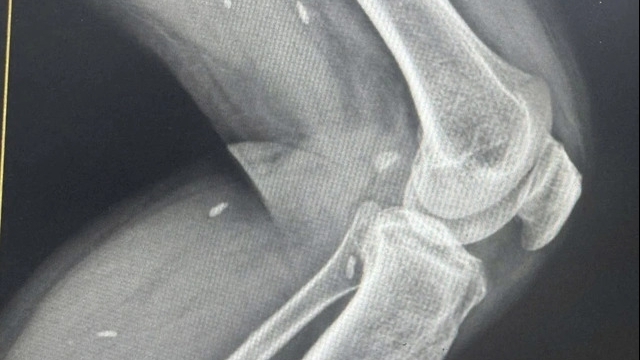

Trong khi các y, bác sĩ tập trung cứu chữa cho nữ bệnh nhân thì xe cấp cứu lại liên tục chạy về viện. Chỉ trong một giờ, 4 trường hợp khác cũng nhập viện cấp cứu vì tai nạn giao thông. Nhiều bệnh nhân nhập viện cùng một thời điểm, đa chấn thương, vô cùng phức tạp, cần phải lập tức cấp cứu và phẫu thuật kịp thời.